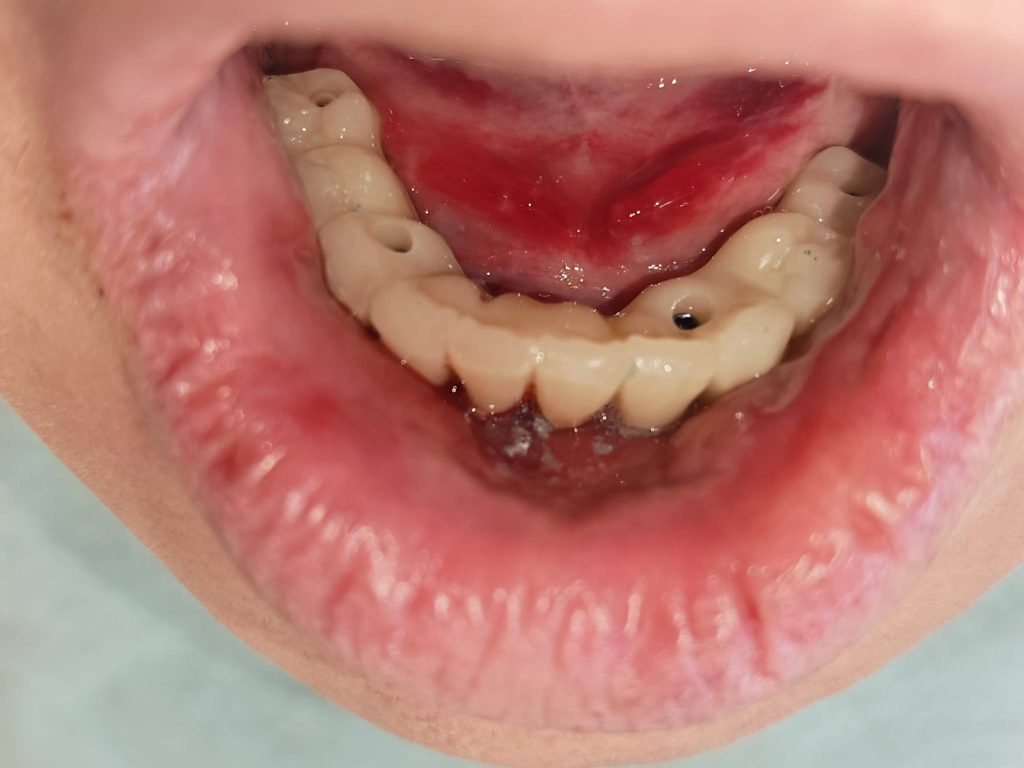

Sistemul Scan LogiQ: Elementul diferențiator al acestui caz a fost utilizarea sistemului Scan LogiQ. Acesta a permis obținerea unei pasivități excelente a lucrării. În termeni medicali, pasivitatea înseamnă că lucrarea se adaptează perfect, fără a exercita tensiuni anormale asupra implanturilor sau osului înconjurător, asigurând longevitatea tratamentului.

Adaptare Predictibilă: Lucrarea se potrivește „la micron” încă de la prima probă.